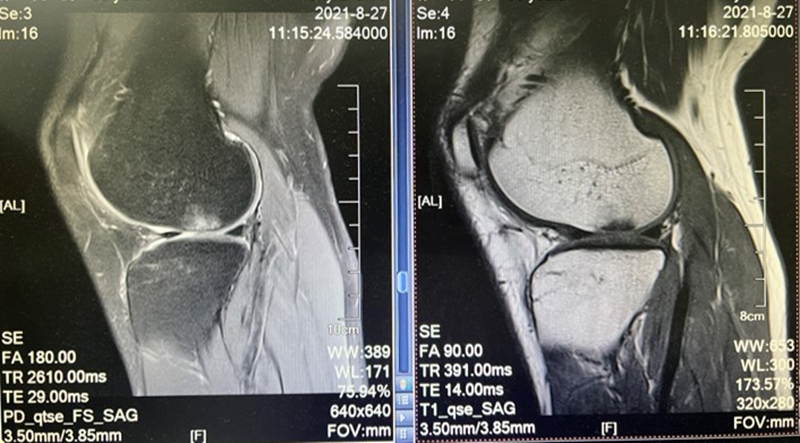

2、体格检查、医学影像与实验室检查

体格检查:关节活动度与对称性,四肢肌肉力量与灵活性,核心肌肉力量与稳定性。

影像学检查:损伤组织定位,组织损伤程度判断